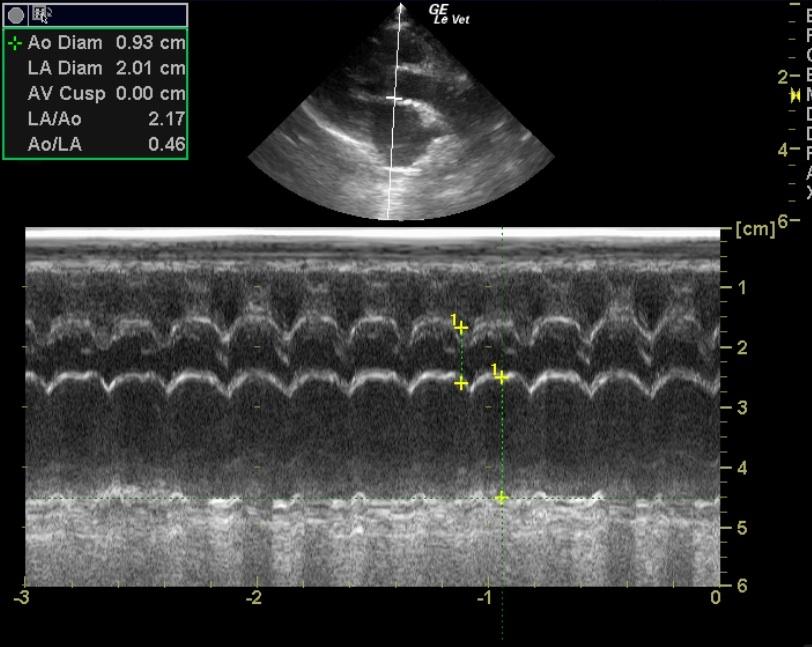

An 11-year-old MN DSH cat presented for sudden onset of hind limb paralysis. CBC and blood chemistry were both within normal limits. Blood pressure measurements were within normal range. MRI revealed lesions suspect for fibrocartilaginous embolism at L6 through the sacrum. Thoracic radiographs showed mild cardiomegaly and a valentine-shaped heart.